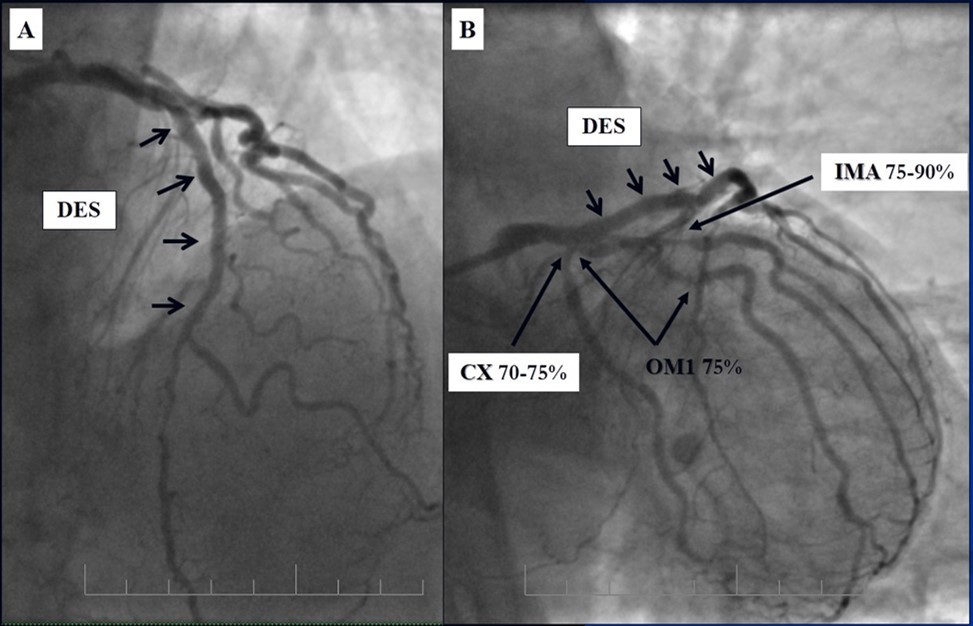

Angiography revealed rare anatomical variation LMCA quadrifurcation (Figure 1, Figure 2), 50% stenosis of the distal part of the LMCA, 40% stenosis of the ostial segment of left anterior descending (LAD) artery and diffuse prolonged 70-75-95% stenosis in mid-segment (Figure 3), 75% stenosis of the ostial segment of the circumflex (CX) artery, 75% stenosis of the ostial segment of the first marginal branch (OM1), 75-90% stenosis of the proximal segment of the intermediate artery (IMA), prolonged diffuse severe 90-95% stenosis of mid-segment of the right coronary artery (RCA) (Figure 4).

Figure 4.A - 50% stenosis of the distal segment of the LMCA; B - 70-75-95% stenosis in mid-segment of the LAD.